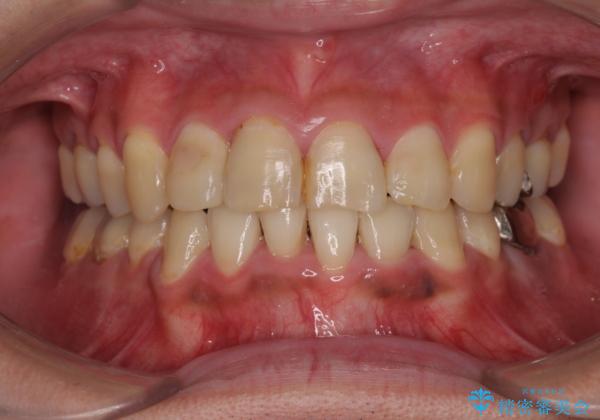

重なって磨きにくい上下の前歯 ワイヤー装置での抜歯矯正

- 前歯のデコボコを改善したいと来院された患者様です。

口元の突出感はないものの、上顎前歯のデコボコが著しかったため、上下顎左右小臼歯4本を抜歯することとしました。